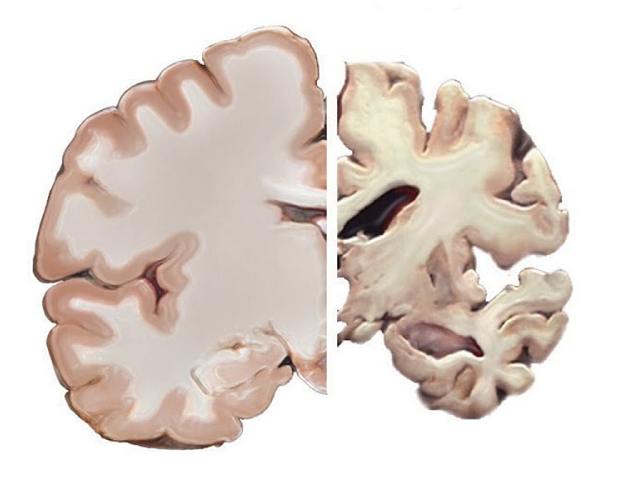

健康大脑(左)和阿兹海默症患者大脑对比